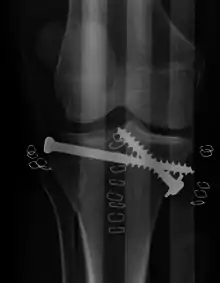

Pain may be managed with NSAIDs, opioids, and splinting.[1][2] In those who are otherwise healthy, treatment is generally by surgery.[1] Occasionally, if the bones are well aligned and the ligaments of the knee are intact, people may be treated without surgery.[2] The surgery usually involves reducing the fractured fragments of the tibia plateau to their anatomical position and fixing them in place with screws only or fixed angle anatomical plates ensuring absolute stability. Implant selection is based on the type of injury. Generally, simple or incomplete fractures (Schatzker type 1) of the plateau are compressed with 6.5mm partially threaded cancellous screws. Complex type fractures will require a plate for enhanced stability. As the tibia condyles articulate with the femur (thigh bone) to form knee joint, any incongruity in the articular surface is unacceptable as it leads to early arthritis. Prolonged immobilization of the knee joint is also not recommended which result in stiffness of the joint and difficult recovery.